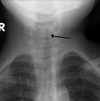

40

¿Qué signo radiológico se menciona para epiglotitis? (Laringotraqueítis/Crup)

Datos en RX de CROUP

Signo de la aguja, campanario, torre de iglesia, punta de lapiz | Tiene varios nombres